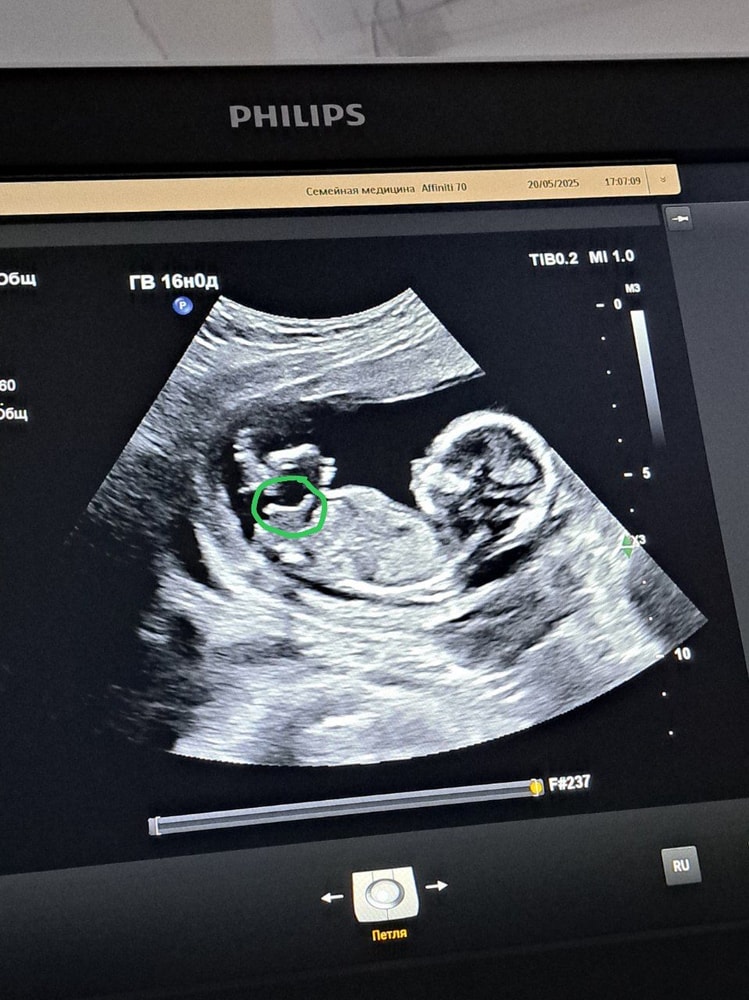

какой пол?

УЗИ, КТГ, доплерочень пожалела что пошла на узи, очень неприятный врач, как будто за бесплатно к ней пришла. начала спрашивать зачем пришла, зачем просто так 🤦🏻 пол толком не назвала, говорит в 20 недель посмотришь 🤦🏻 фото попросила сделать, расцокалась блин, хотя это заняло несколько секунд.... короче, кто в домике живёт? и что это торчит наверх? все нормальные узисты пол снизу смотрят, а она на этом сроке бугорок сбоку ещё высматривала 🤦🏻

Если б это фото было 12-13 недели, тогда бы девочку можно было предположить , но боюсь, что так уже не смотрят и фото просто для красоты

На этом сроке уже не информативно смотреть с боку, смотрят действительно между ног. Торчать там может что угодно.